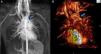

A nine-year-old girl was referred to the pediatric cardiology department for a cardiac murmur and Turner syndrome. She was asymptomatic and presented an ejection systolic murmur at the left sternal border. The electrocardiogram (ECG) showed right bundle branch block and the echocardiogram showed no intracardiac shunts, right ventricular dilatation with abnormal motion of the ventricular septum, and normal biventricular function. Cardiac catheterization revealed a normal heart with Qp/Qs 1:1. She continued to be followed in the pediatric cardiology clinic. At the age of 13 years she still presented right ventricular dilatation with an intact interatrial septum. MRI (Figure 2A and B) showed a partial anomalous pulmonary venous connection to the brachiocephalic vein, intact interatrial septum, right ventricular dilatation and Qp/Qs 1.6:1. She underwent cardiac surgery with a good outcome. This case highlights the potential role of MRI in these anomalies and is a reminder that although it is still the gold standard, cardiac catheterization when performed incorrectly may give inaccurate information. One of the key points is to take venous blood samples at various levels in order to obtain precise results.